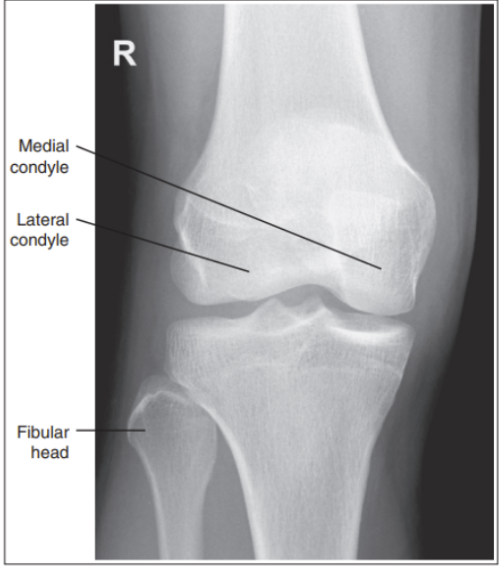

What are the issues with this AP knee?

Intercondylar fossa is shown

Knee is flexed and not straight